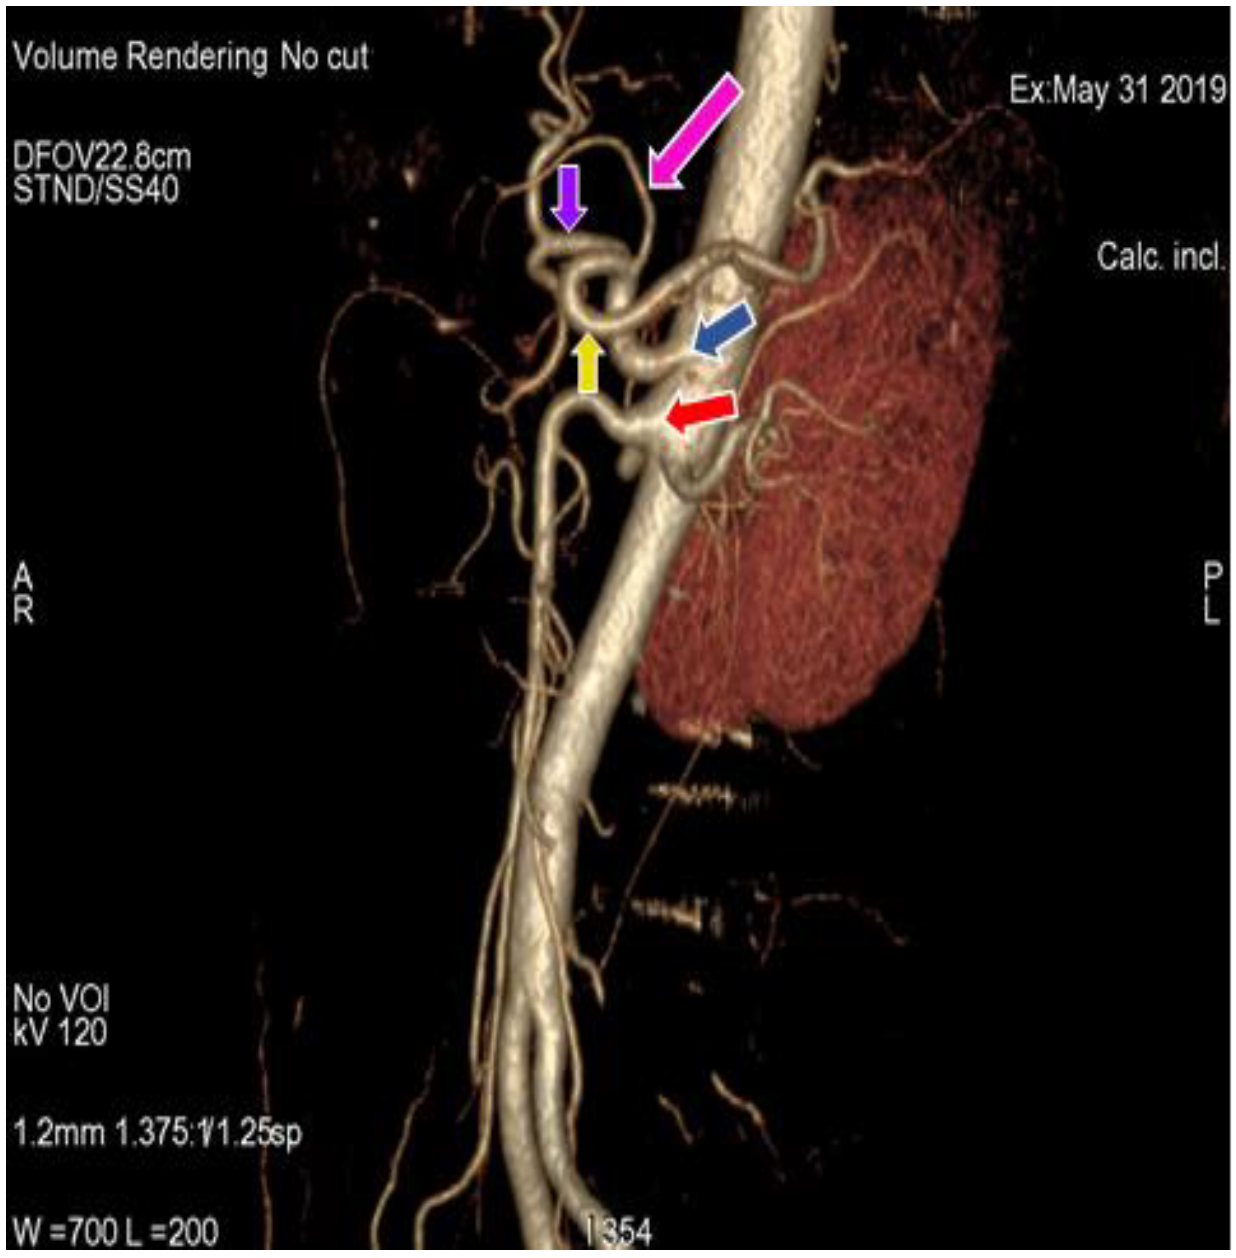

3.1. Variation in Origin and Branching Pattern of Celiac Trunk

3.2. Variation in Origin and Branching Pattern of Hepatic Artery